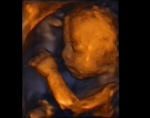

Vypočtěte si v naší těhotenské kalkulačce, kdy Vás čekají ultrazvuky, kdy obdržíte těhotenskou průkazku, kdy se podrobíte triple testu, kdy se vyšetřuje streptokok, kdy se provádí amniocentéza, kdy byste si měla nachystat věci do porodnice, kdy nastupujete mateřskou dovolenou.